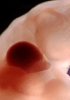

Carnegie Stage 14 (32 post-ovulatory days)

Most embryos at stage 14 are approximately 32 postovulatory days old and measure 5-7 mm in length. Distinguishing criteria for this stage include an open lens pit with invagination of the lens disc and elongated and tapering upper limb buds. The otic vesicle with a well-defined endolymphatic appendage is also a hallmark of this stage.